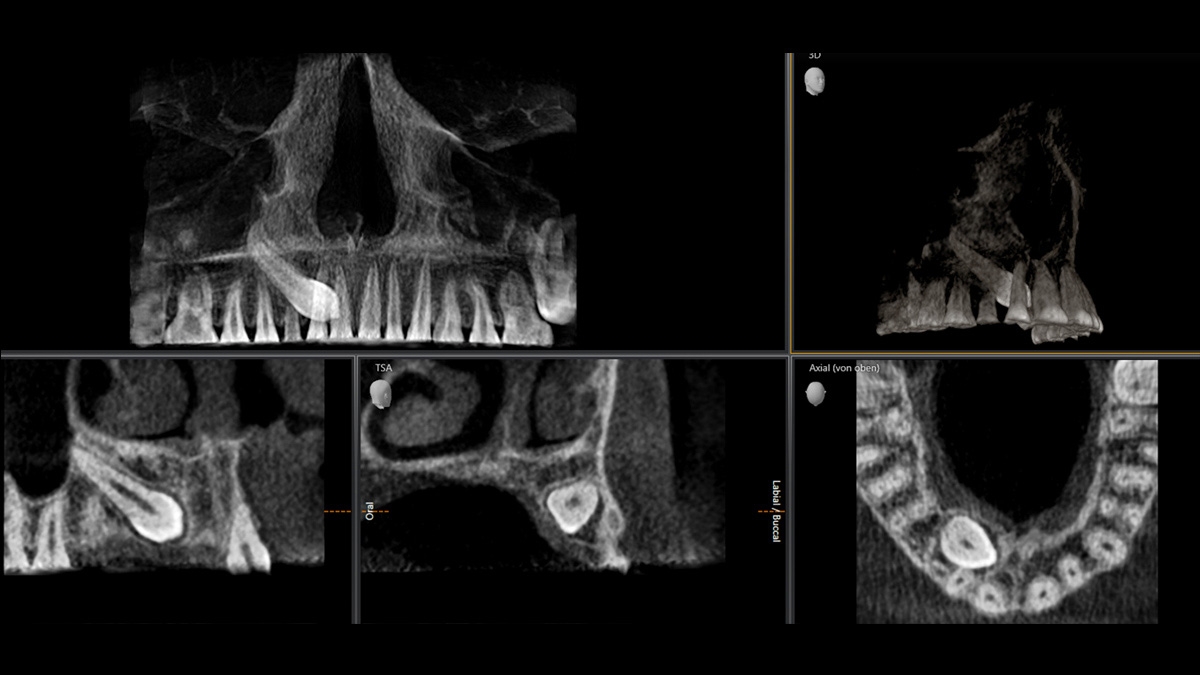

Exemples imagerie panoramique 3D

Localisation d'une canine déplacée 5 x 5,5 cm a 3µSv